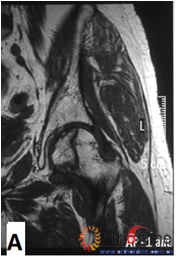

图2-1

图2 依据股骨头外侧柱存留情况,股骨头坏死的分型。(图2-1)分为Ⅰ型(外侧柱全部存留)(A)MRI图像显示;(B)7年后CT显示股骨头仍未塌陷;(图2-2)Ⅱ型(外侧柱部分保留)(A)MRI显示外侧皮质存留;(B)4年后CT显示股骨头仍未塌陷;(图2-3)Ⅲ型(坏死带穿透股骨头);(A)MRI显示坏死带;(B)2年后股骨头塌陷

Fig 2 According to preservation of the lateral pillar, the necrosis was divided into three types. (Fig 2-1)Type Ⅰ: Whole lateral pillar preserved (A) MRI showing; (B) no collapse occurred seven years later by CT showing. (Fig 2-2)Type Ⅱ: Preservation of the partial lateral pillar, (A) MRI showed the preservation of the lateral cortical bone; (B) no collapse of the femoral head four years by CT. (Fig 2-3)Type Ⅲ: the necrotic line pass through the cortical bone and bone morrow ;(A) MRI showed the necrotic line; (B) collapse of the femoral head occurred two year later.